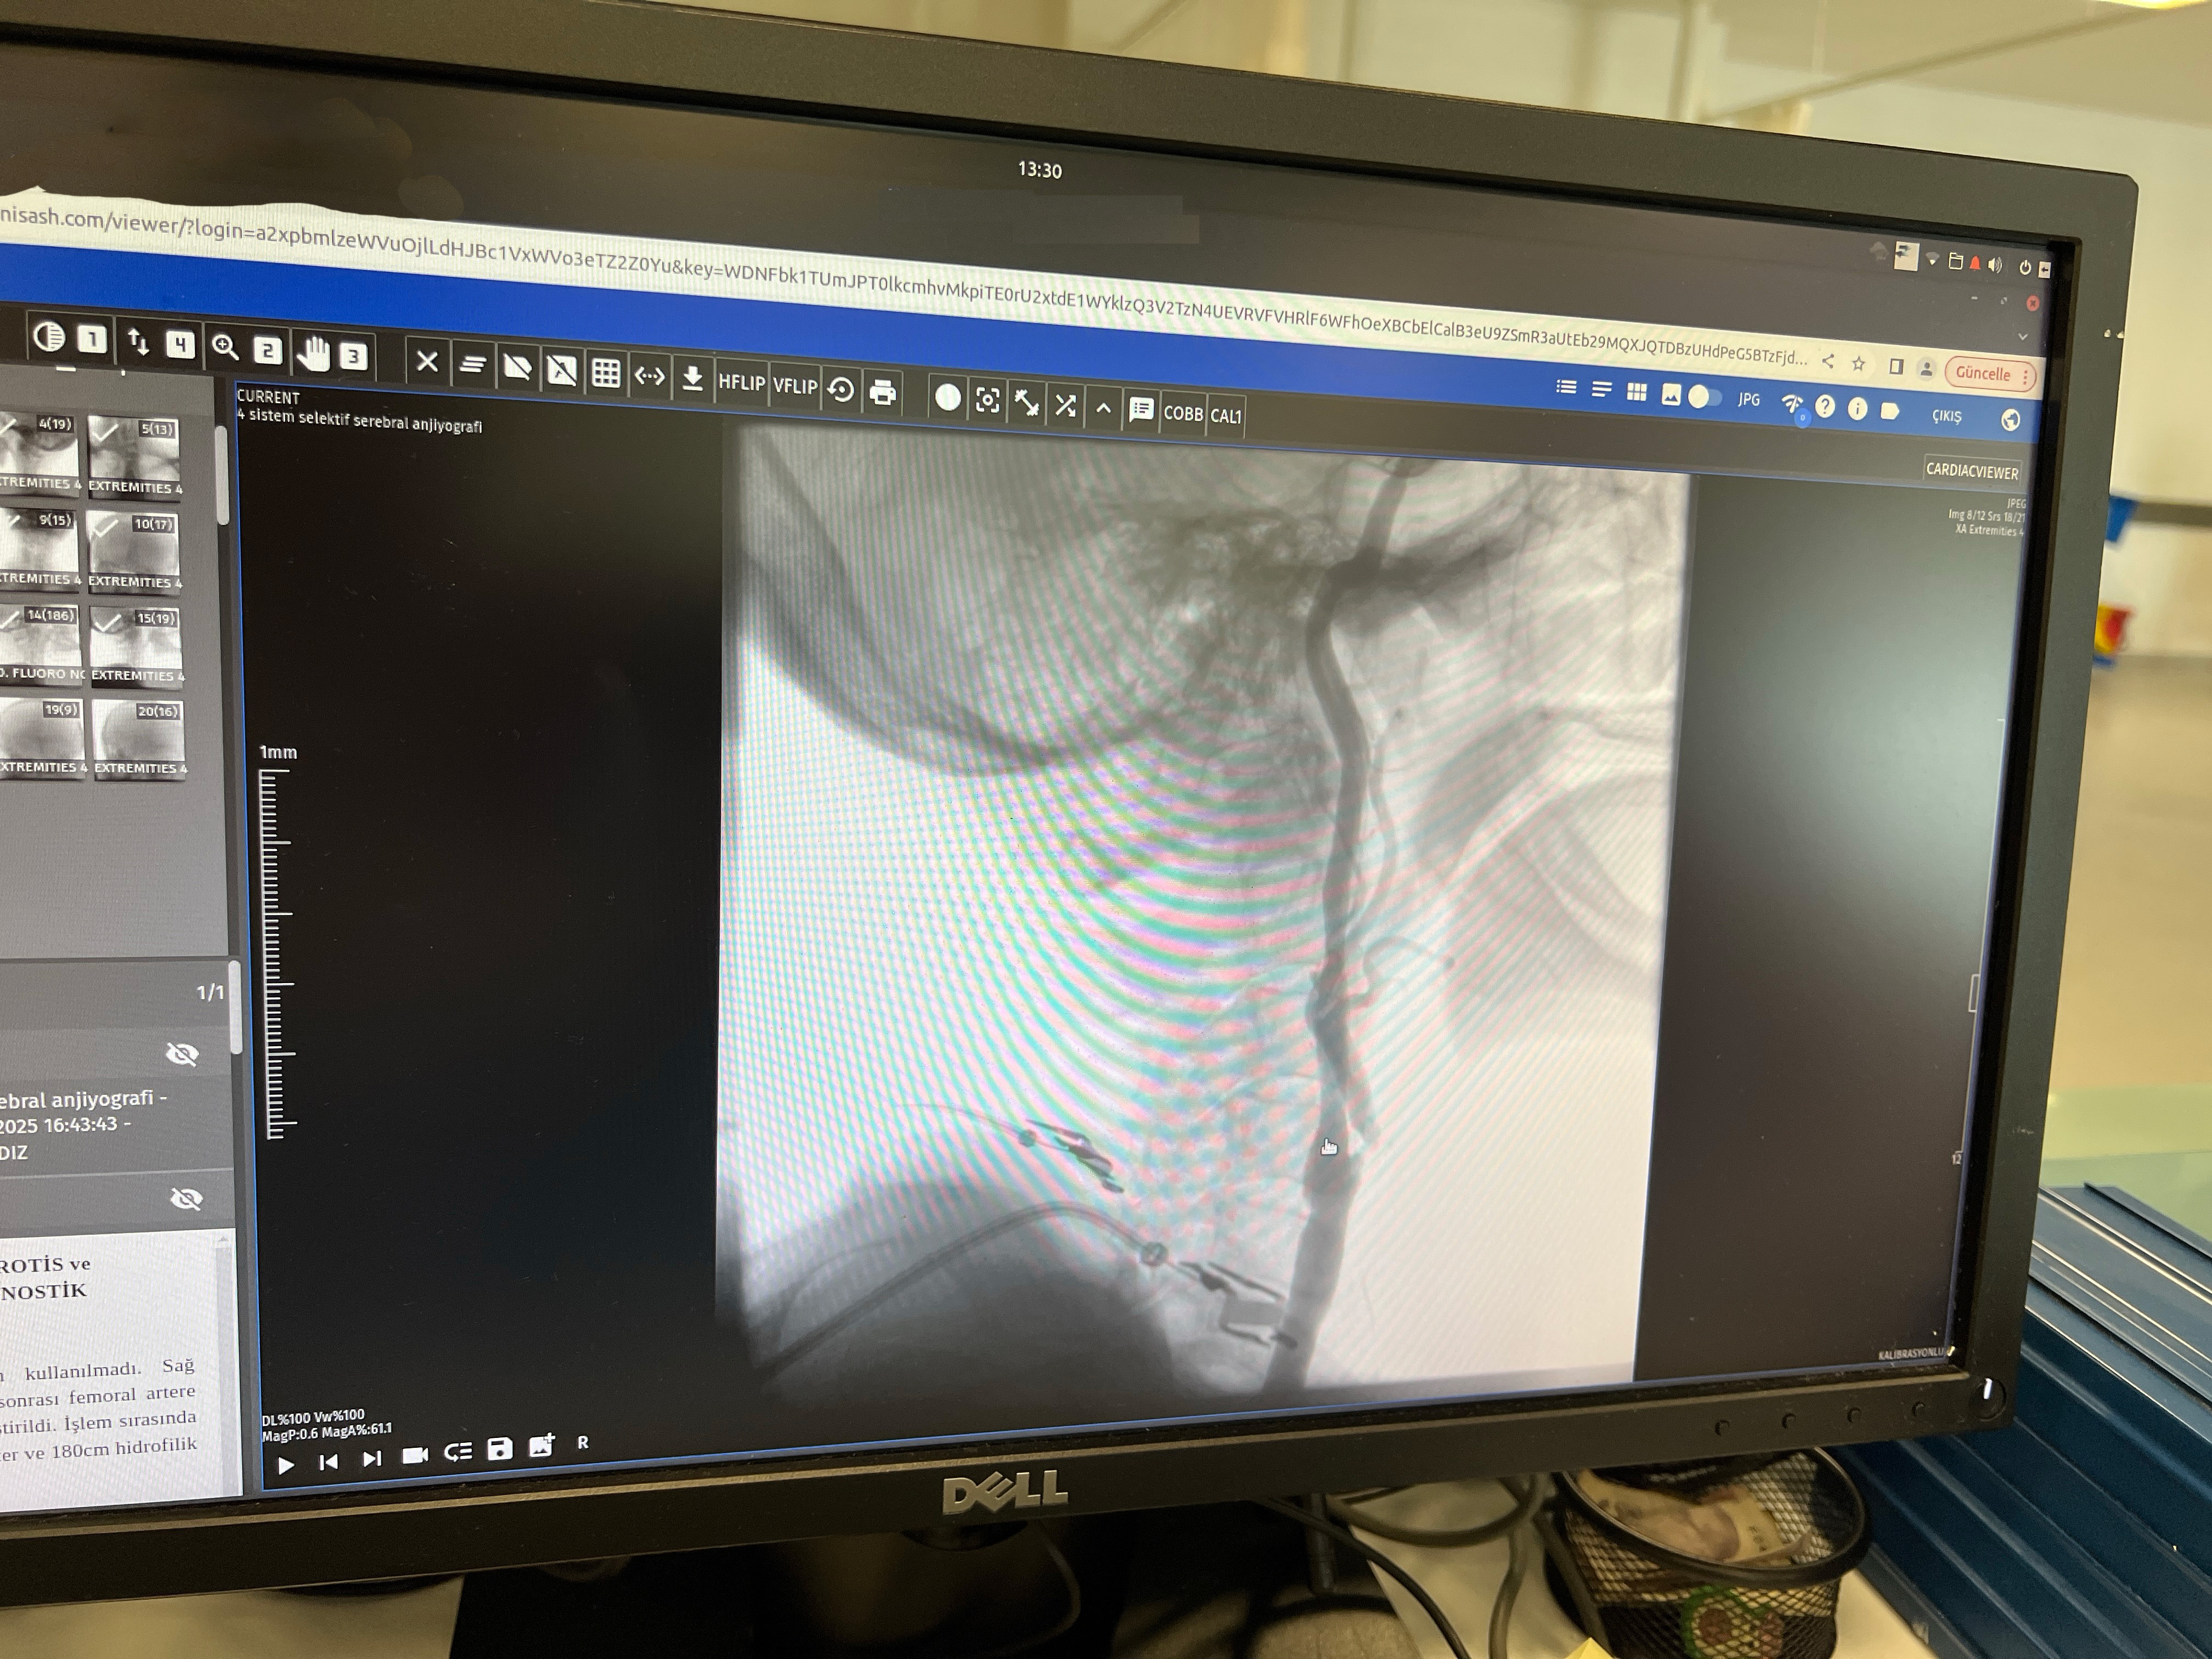

Stentleme işlemi, femoral arterden (kasık atardamarı) girilerek ince kateterler ve özel stentler aracılığıyla daralmış damarları açmayı kapsıyor. Böylece beyne giden kan akışı güvence altına alınarak felç riski büyük ölçüde azaltılıyor. İşlemin ameliyatsız olması, hastaların kısa sürede normal yaşamlarına dönmesini sağlıyor. Doç. Dr. Gündüz, “İşlem sorunsuz geçerse hasta ertesi gün taburcu olabiliyor. Hem konforlu hem hızlı bir iyileşme süreci sağlanıyor” dedi.

Uzmanlar, bu işlemin yalnızca donanımlı merkezlerde ve deneyimli hekimler tarafından yapılabileceğini belirtiyor. Doç. Dr. Sezer Eryıldız, “Girişimsel anjiyografi cihazı olan ve yeterli vaka deneyimine sahip merkezlerde güvenle uygulanabilir” diye konuştu.